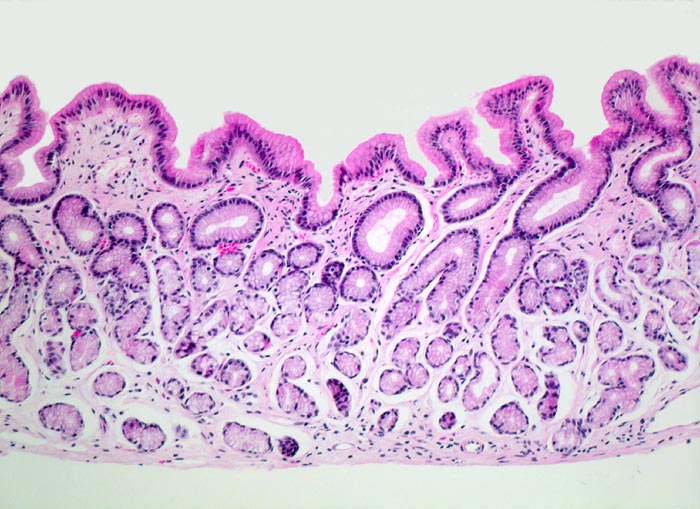

Das Unterrichtspräparat zeigt eine Helicobacter-Gastritis mit intestinaler Metaplasie. Histologisch ist die Typ B Gastritis charakterisiert durch eine chronische (Plasmazellen und Lymphozyten) und aktive (neutrophile Granulozyten) Entzündung. Das Ausmass der chronischen Entzündung und die Entzündungsaktivität werden gemäss Sydney Klassifikation in drei Schweregrade unterteilt (z.B. mässiggradige chronische, stark aktive Gastritis). Fakultativ können Lymphfollikel, eine intestinale Metaplasie mit/ohne Dysplasie und/oder Drüsenatrophie hinzukommen. Die Erreger (Helicobacter pylori) kolonisieren den protektiven Schleimfilm auf der Magenmukosa (> 3330) (> 9968) und sind dort mittels Spezialfärbung (Giemsa C) mikroskopisch nachweisbar. Unmittelbar im Bereich der intestinalen Metaplasie sind aufgrund des veränderten Milieus meist keine Bakterien nachweisbar. Unter Einnahme von Säurehemmern oder Antibiotika verringert sich die Sensitivität des Bakteriennachweises in der Biopsie aufgrund der schnellen Reduktion der Bakterienanzahl ebenfalls. Nach erfolgreicher Eradikation verschwindet in der Regel die aktive Entzündung innert Wochen. Chronische Entzündung und Lymphfollikel bleiben jedoch länger nachweisbar und geben einen Hinweis auf eine abgelaufene Helicobactergastritis.

• Vier Magenschleimhautbiopsien (Oberstes: Antrum/Corpusübergang mit intestinaler Metaplasie, zweitoberstes und unterstes: Antrumschleimhaut mit intestinaler Metaplasie, zweitunterstes: Corpusschleimhaut mit intramukosalem Lymphfollikel ohne Metaplasie).

• Schwere chronische (dichtes lymphoplasmazelluläres Entzündungsinfiltrat in der Lamina propria), stark aktive (neutrophile Granulozyten in der Lamina propria und im Epithel mit Ausbildung von Mikroabszessen) Gastritis.

• Typisch für Helicobactergastritis: intramukosale Lymphfollikel

• Intestinale Metaplasie der Antrumschleimhaut: Basophile (bläuliche) Drüsenschläuche mit Becherzellen sowie einzelnen Paneth'schen Körnerzellen mit rot granuliertem Zytoplasma im untersten Schleimhautfragment. Die metaplastische Schleimhaut erinnert stark an Kolonschleimhaut.